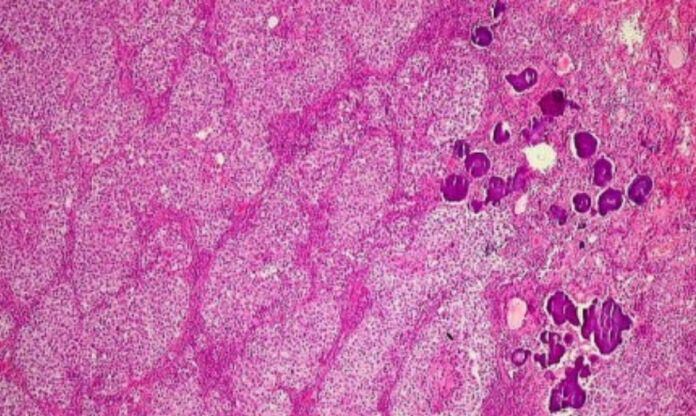

Foram analisadas amostras de 17 crianças diagnosticadas entre 2000 e 2021 — 11 tumores ovarianos, três testiculares e três do sistema nervoso central — além de tecidos normais de comparação. A equipe avaliou a expressão de 800 genes ligados à imunidade e identificou perfis imunológicos distintos para cada subtipo tumoral, como uma “assinatura biológica” capaz de prever comportamento clínico e resposta ao tratamento.

Nos disgerminomas, tumores exclusivos do ovário, observou-se grande infiltração de linfócitos T CD8+ e aumento de checkpoints imunológicos, sugerindo boa resposta a inibidores de checkpoint já usados em cânceres de adultos. Já os tumores do saco vitelino exibiram um ambiente mais agressivo, com células T exauridas e alta expressão de moléculas como CD24 e PVR, associadas à evasão imunológica e resistência à quimioterapia. Nos carcinomas embrionários também foi identificado aumento do CD24, reforçando seu potencial como biomarcador-chave para novas terapias direcionadas ao câncer infantil raro.